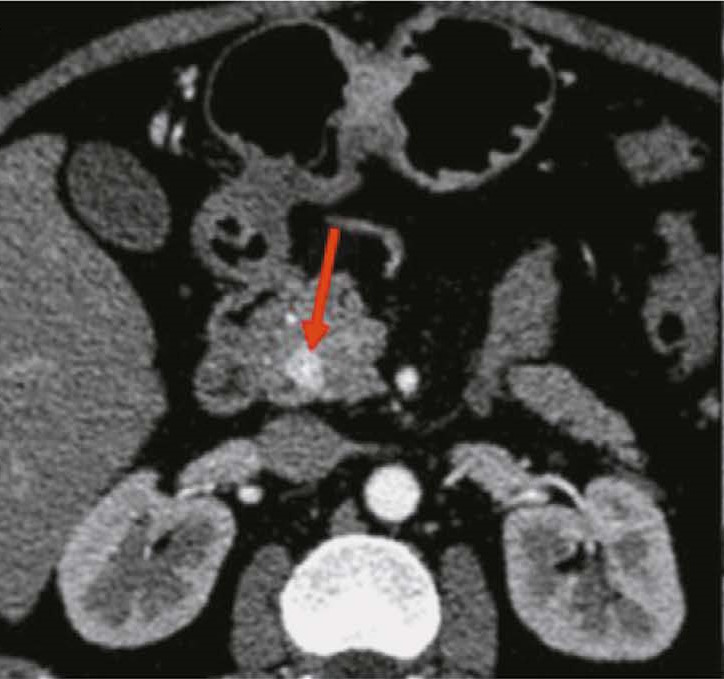

Neuroendocrine tumors of stomach and pancreas: diagnostic potential of radiomics, issues, and solutions

BACKGROUND: Radiomics is currently a promising and prospective tool for diagnosing and treating neuroendocrine neoplasms at various sites. This method is often used for differential diagnosis of gastrointestinal neuroendocrine tumors with other neoplasms at this site.

AIM: The aim of the study was to evaluate the potential of radiomics for differential diagnosis of neuroendocrine tumors of stomach and pancreas.

MATERIALS AND METHODS: The study included data of 12 patients with morphologically proven neoplasms of the stomach (6 with neuroendocrine tumors and 6 with adenocarcinomas) and data of 22 patients with morphologically proven neoplasms of the pancreas (11 with neuroendocrine tumors and 11 with adenocarcinomas). All patients underwent abdominal computed tomography (CT) with intravenous contrast enhancement prior to treatment at the Russian Scientific Center of Roentgenology and Radiology. Radiomics parameters were calculated for the area of gastric and pancreatic tumor manually segmented in the native phase of the CT scan. The results were processed and statistically analyzed using Microsoft Office Excel and R-Studio, a free, open-source software development environment for the R programming language.

RESULTS: CT scan examples demonstrate typical and atypical visual signs of neuroendocrine tumors of stomach and pancreas, contrast enhancement characteristics, location and structure of neoplasms. Fifteen radiomics parameters were identified that were statistically significantly different between gastric neuroendocrine tumor and gastric adenocarcinoma. In pancreas, neuroendocrine tumors differed significantly from adenocarcinomas in 14 radiomics parameters.

CONCLUSIONS: Neuroendocrine tumors of stomach and pancreas are rare neoplasms that are mostly asymptomatic and difficult to visualize due to their small size and contrast enhancement characteristics. Texture analysis may be a promising approach to differentiate gastrointestinal neuroendocrine tumors from other neoplasms at these sites, especially in the view of the difficulty in obtaining a biopsy.